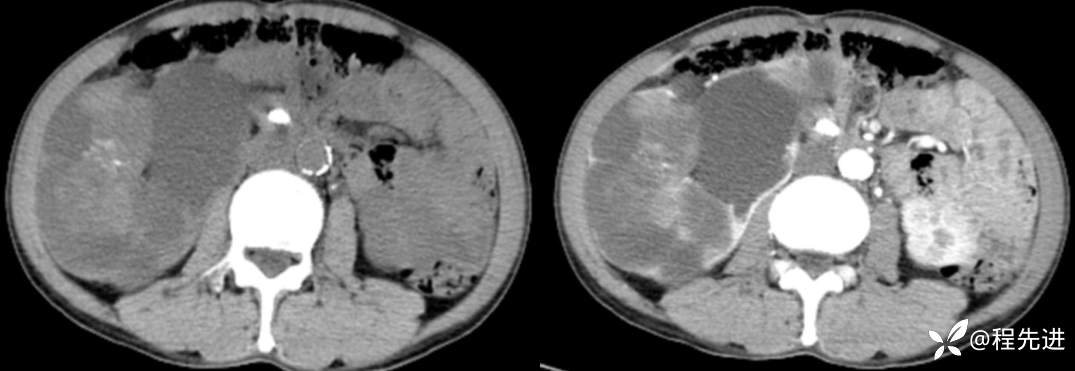

CT平扫+增强

左平扫,右增强